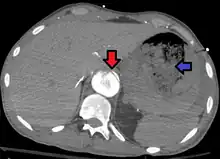

Aorto enteric fistula and aortic dissection of the thoracic aorta. Arrow shows the flap in the aorta. Heterogeneity is blood in the stomach

An aortoenteric fistula is a connection between the aorta and the intestines, stomach, or esophageus.[1] There can be significant blood loss into the intestines resulting in bloody stool and death.[1] It is usually secondary to an abdominal aortic aneurysm repair. The third or fourth portion of the duodenum is the most common site for aortoenteric fistulas, followed by the jejunum and ileum.